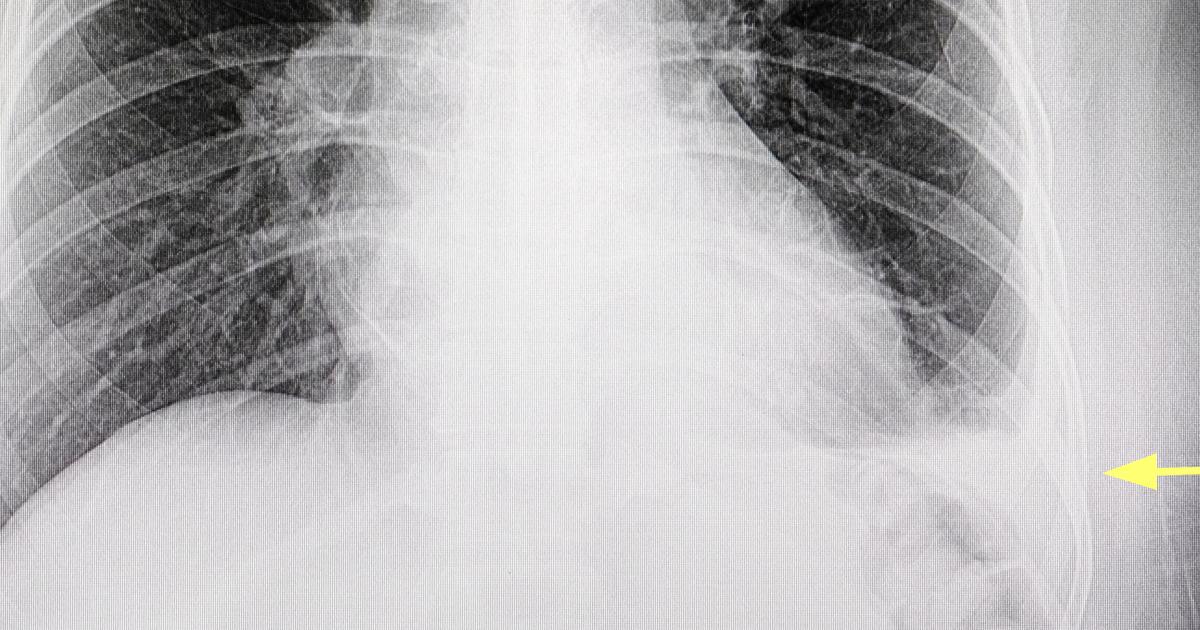

Pleural Effusion

Pleural effusion can affect an individual who has cancer of the peritoneum as a symptom of their malignancy. Pleural effusion occurs when excess fluid builds up in between the membranes that cover and protect an individual's lungs. A healthy individual has a small quantity of fluid that remains between the pleura to lubricate the area and help with breathing. However, individuals who have a malignant growth in their peritoneum can experience an accumulation of too much protein-rich fluid in the pleura. This symptom happens when the malignant cells infiltrate the lymphatic vessels and lymph nodes in the abdominal and chest regions. The lymph nodes and lymph vessels are responsible for absorbing fluid from tissues around the body when there is an excess. However, malignant cells can obstruct the process of fluid absorption and lymphatic circulation in certain affected parts of the body. When peritoneal cancer has this effect in the chest and abdominal region, the fluid begins to accumulate in nearby tissues like the pleura because it has no place to go. Pleural effusion in peritoneal cancer patients is especially indicative of a more advanced stage of malignancy.